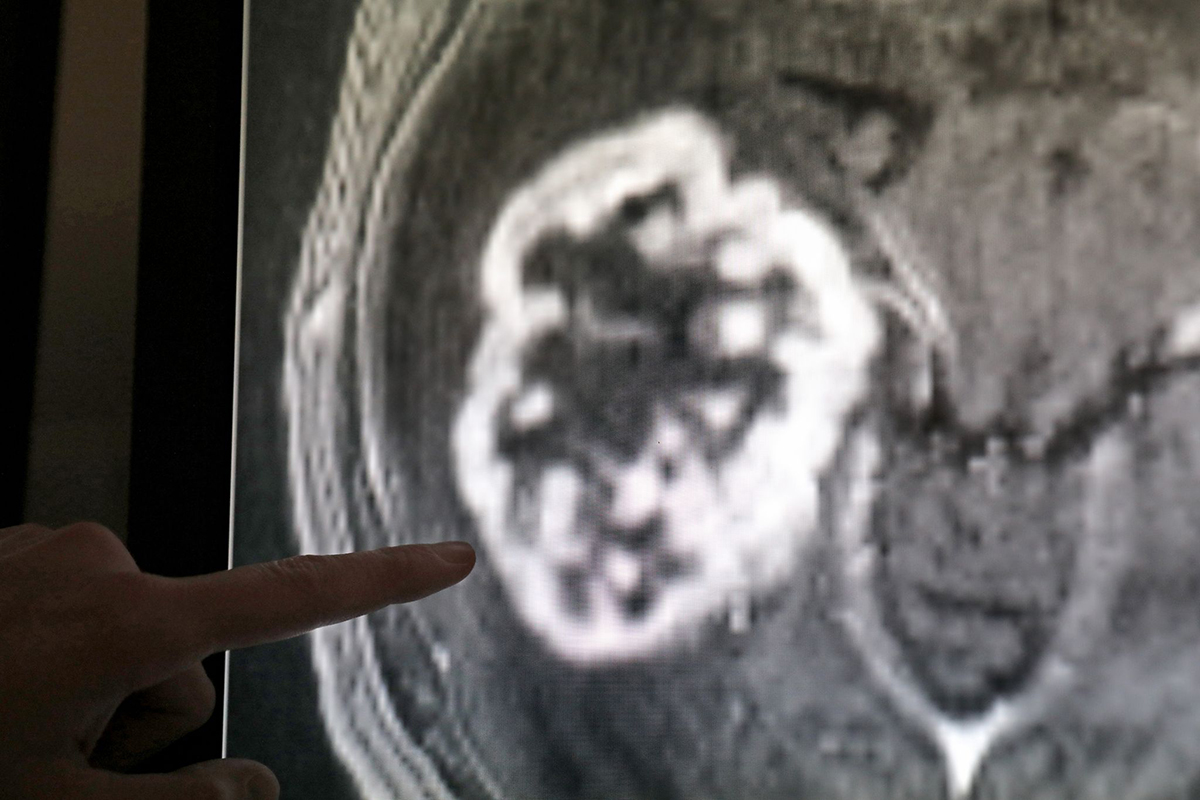

Krebskrankheiten. Foto: Bernd Wüstneck/dpa-Zentralbild/dpaMainz. Kopf-Hals-Tumoren betreffen in Rheinland-Pfalz mehr Männer als Frauen, jedoch gibt es positive Trends, wie das Institut für digitale Gesundheitsdaten in Mainz mitteilte. Im Jahr 2024 wurden 429 Männer und 213 Frauen mit diesen Tumoren diagnostiziert, wobei 164 Männer und 73 Frauen daran starben. Männer sind nach wie vor häufiger betroffen als Frauen.